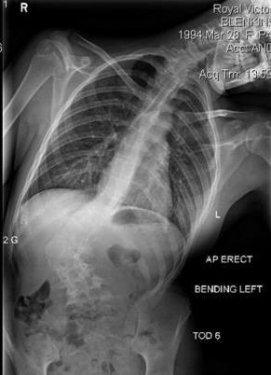

Manken Zoe Blenkinsop dünyaya skolyoz rahatsızlığıyla geldi. Sırtındaki omuru S şeklinde eğri olan genç kız, uzun süre ayağa kalkmakta bile zorlandı.Her seferinde büyük acılar çeken genç kızın sırtında bir yumru oluştu.

11 yaşında teşhis konulan kıza operasyon yapılabilmesi için kemiklerinin yerleşmesi gerektiği söylendi.

Bunun için de 18 yaşına kadar beklemesi gerektiği anlatıldı.